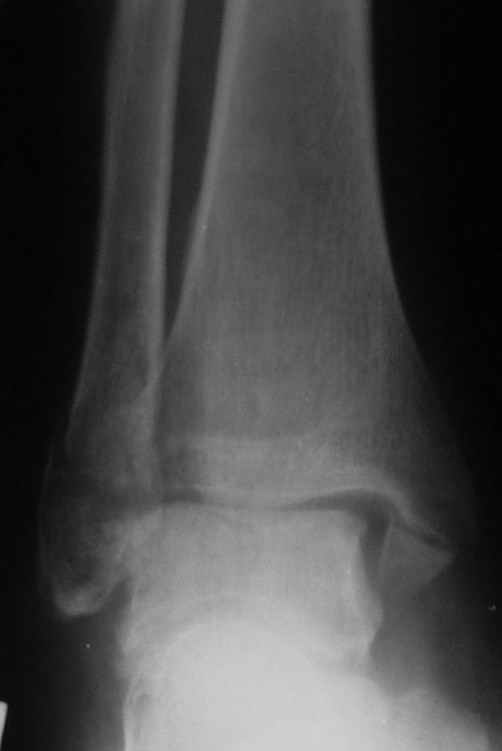

Ниже рентгенограммы

До операции 28 июля

Через месяц

Боковой через месяц

Риторический вопрос - в каком руководстве рекомендован такой способ остеосинтеза наружной лодыжки?

Очевидно, такой результат операции был запрограммирован. При невосстановленной длине и практически нефиксированной малоберцовой кости (этот кортикальный винт - как карандаш в стакане), при неустраненном подвывихе, невправленной и тоже нефиксированной внутренней лодыжке нет стабильной вилки сустава. Если такую операцию сделать даже сразу, а не через 4 месяца, то результат ожидаем

тот же.

Вообще говоря, такое повреждение вполне успешно можно лечить без операции - если 6 недель подержать в гипсовом "сапожке" с хорошо устраненным подвывихом. Вероятное несращение внутренней лодыжки не обязательно компрометирует результат.